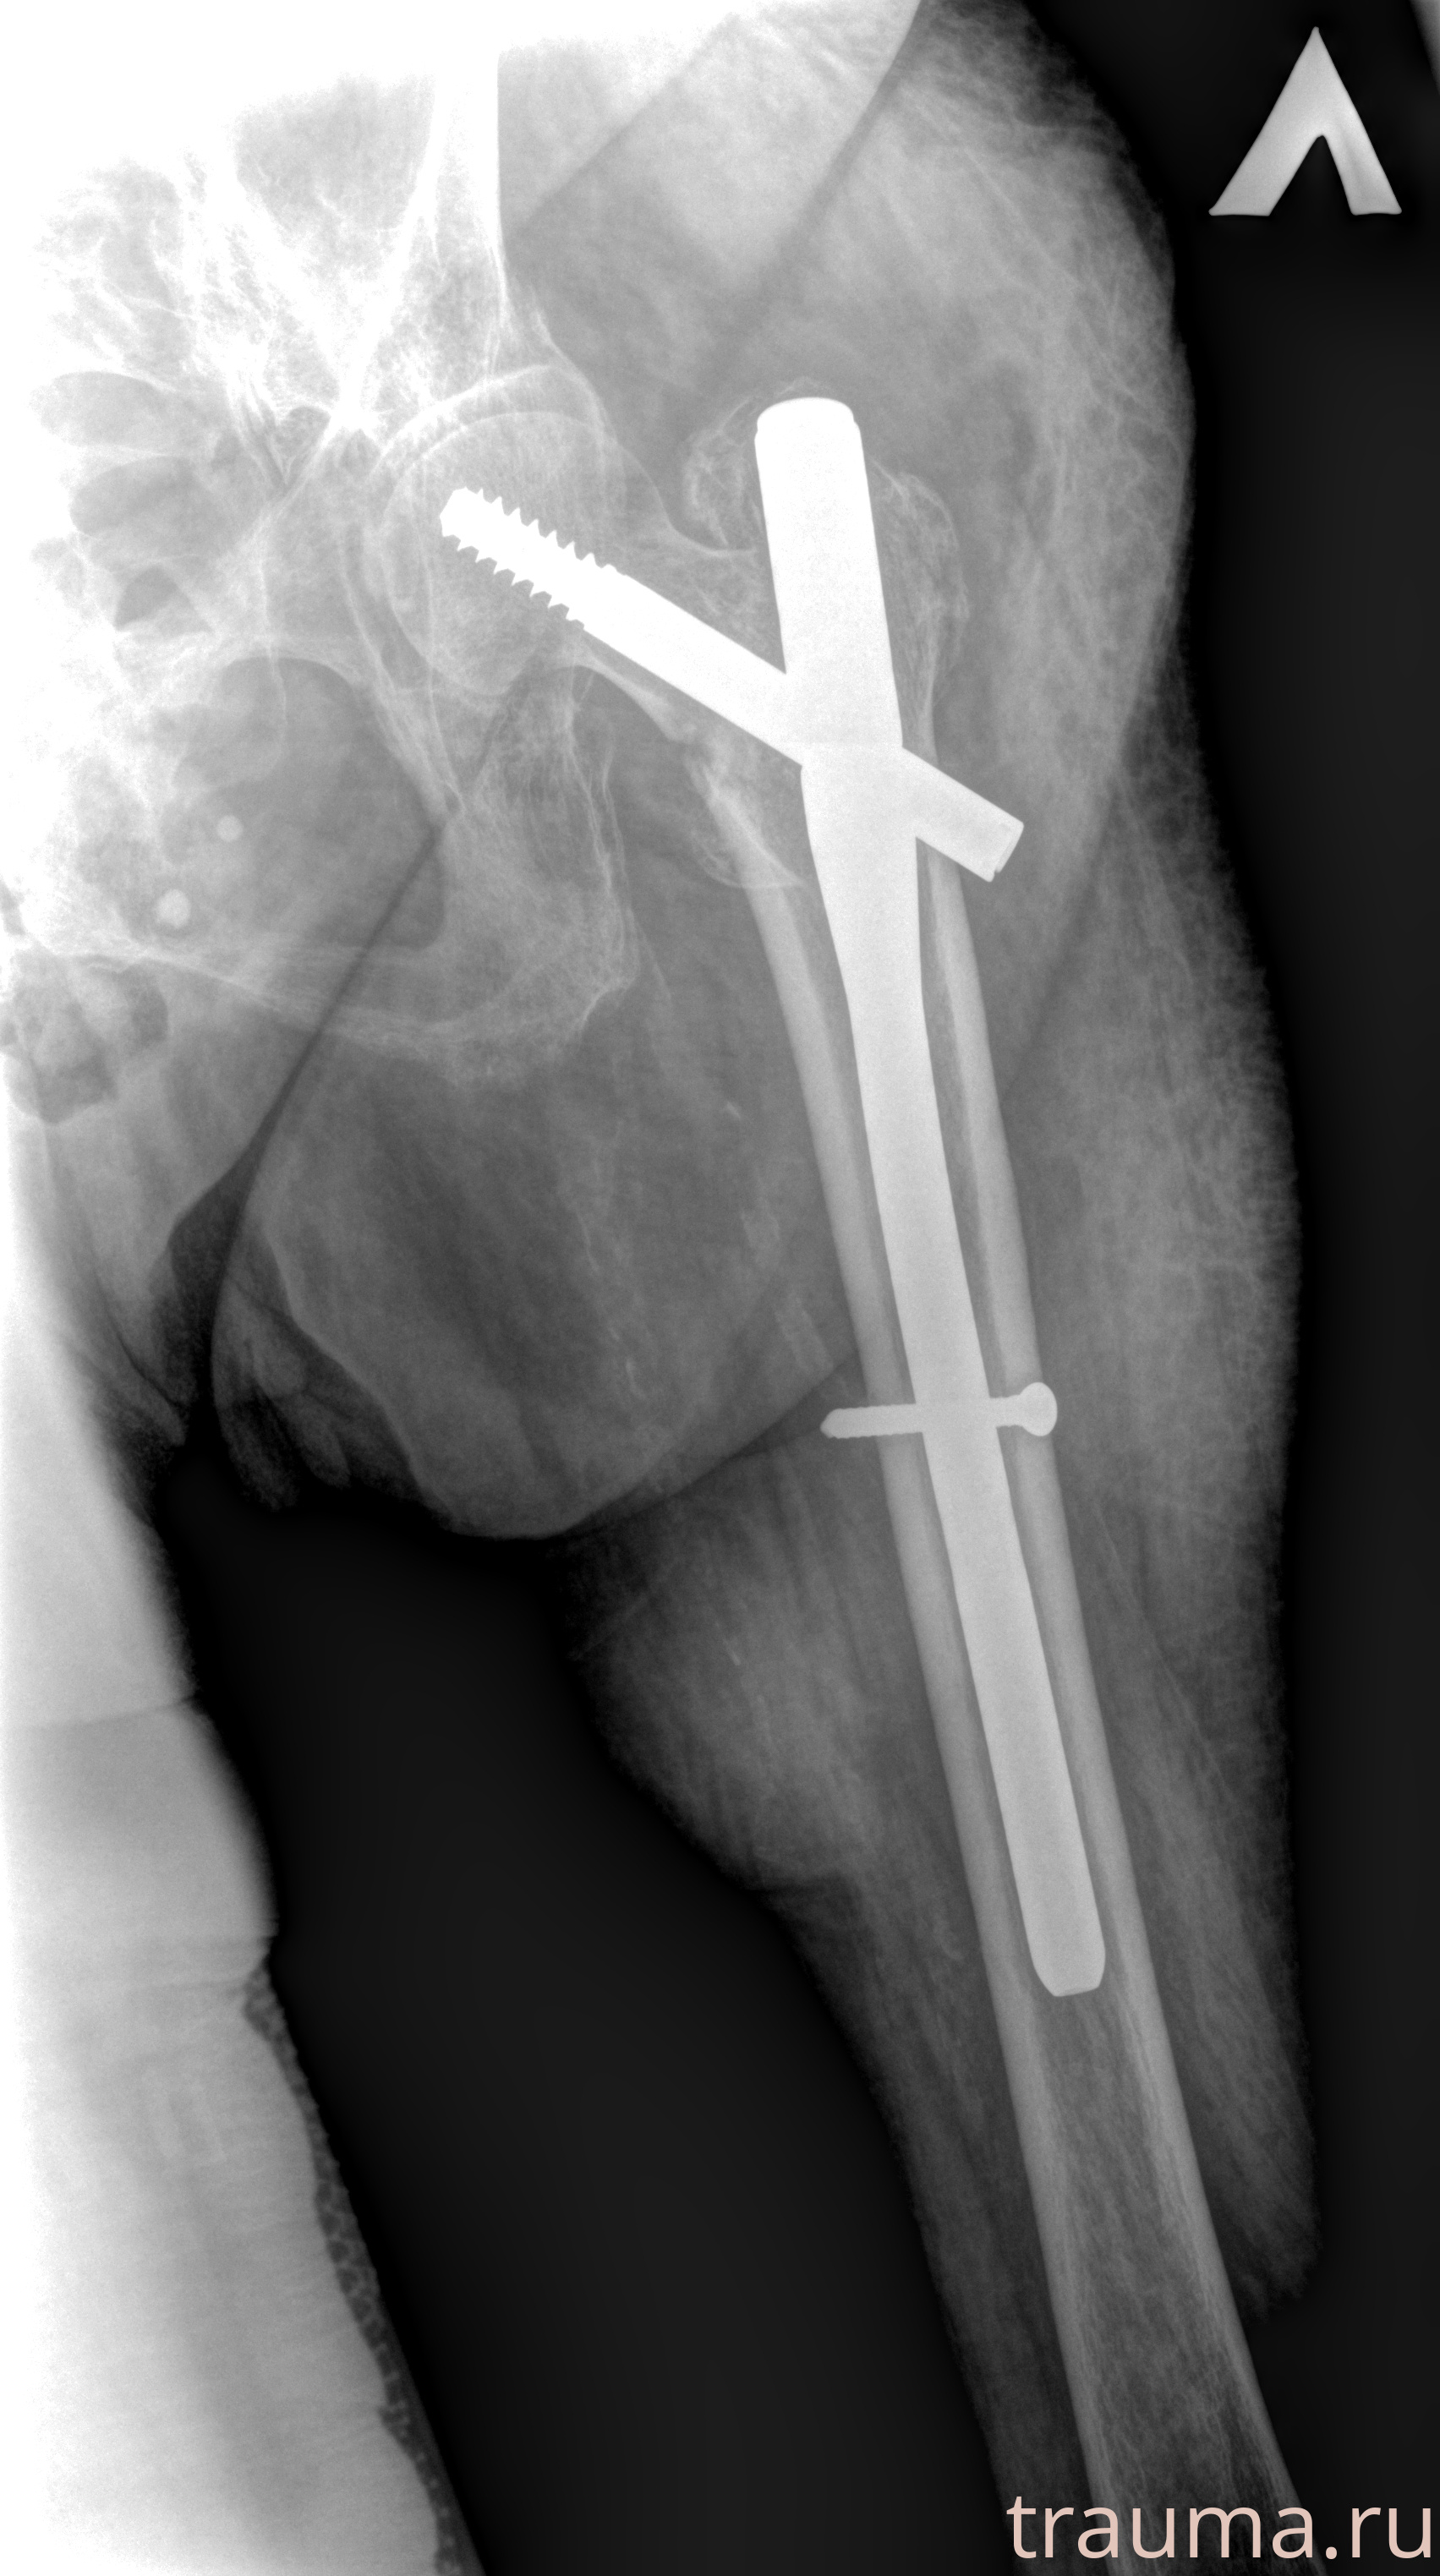

Рентгенограммы

Рентген на дому: по вашему адресу приезжает врач-рентгенолог, травматолог-ортопед с мобильным рентгеновским аппаратом, проводит диагностику травмы или заболевания, делает необходимые рентгенограммы, дает рекомендации по дальнейшему лечению. Получить качественные снимки в домашних условиях возможно благодаря уникальной методике, разработанной МосРентген Центром для института  Склифосовского